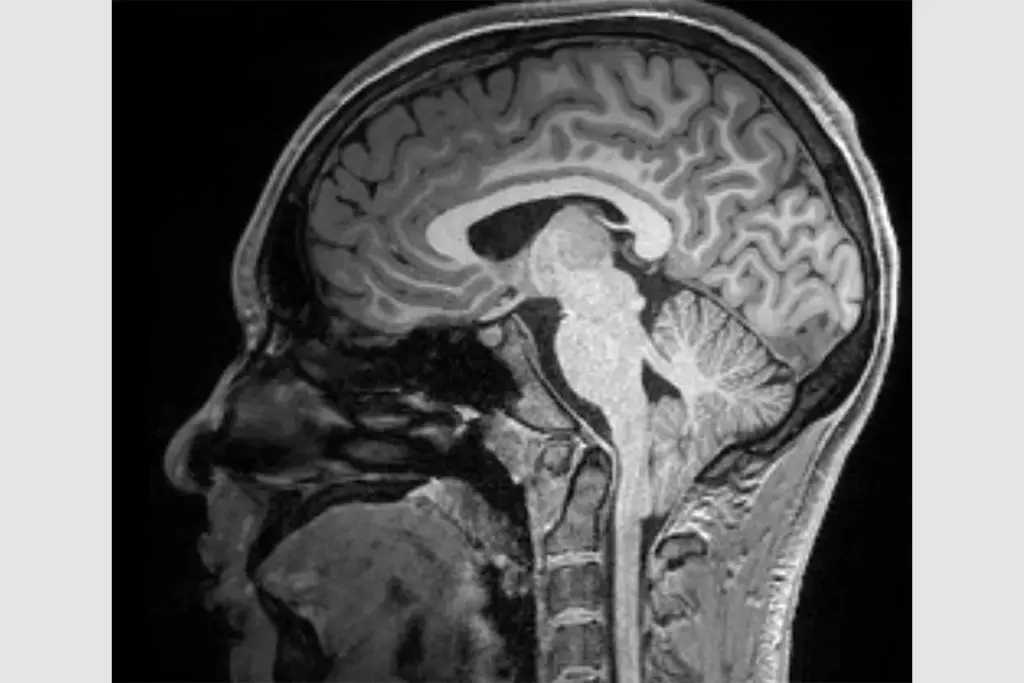

The clinical presentation of pituitary tumors is remarkably diverse, ranging from subtle hormonal changes to dramatic neurological deficits. This diversity stems from the dual nature of the pathology: the physical presence of the mass and the potential for hormonal dysregulation. Patients may endure symptoms for years before a diagnosis is reached, as the manifestations often mimic other common conditions. Recognizing the signs of pituitary tumors involves identifying both the mass effects caused by the tumor’s size and the systemic effects caused by hormone excess or deficiency. The symptoms are rarely uniform; they depend heavily on the specific cell type involved and the direction of tumor growth. This section details the myriad ways a pituitary tumor can impact the body, exploring the spectrum from visual disturbances to metabolic syndromes, providing a comprehensive guide to the warning signs that necessitate medical attention.

As a pituitary tumor expands within the confined space of the sella turcica, it inevitably encounters surrounding anatomical structures. The pressure exerted by the tumor on these structures is referred to as mass effect. This is the primary mechanism of symptoms for non-functional macroadenomas. The headache associated with pituitary tumors is often non-specific but persistent, resulting from the stretching of the dural lining of the sella. Unlike migraines, these headaches may not respond well to standard analgesics and can be located in the frontal or retro-orbital regions. As the tumor grows upward, it impinges on the optic chiasm, and lateral growth can affect the cavernous sinuses, leading to a distinct set of neurological signs that serve as critical red flags for clinicians.

The most classic sign of a large pituitary tumor is visual loss, specifically bitemporal hemianopsia. This condition involves the loss of peripheral vision in both eyes, creating a tunnel vision effect. It occurs because the crossing fibers of the optic nerve, which carry information from the temporal visual fields, are compressed by the tumor pushing upward from the sella. Patients may not notice this loss initially, often bumping into door frames or having difficulty driving. In severe cases, visual acuity itself can diminish, leading to blindness if the pressure is not relieved. Prompt surgical decompression can often restore vision, highlighting the urgency of recognizing this symptom.

Cranial Nerve Compression

The pituitary gland sits directly beneath the optic chiasm, where the optic nerves cross. Large tumors push upward, compressing these nerves and causing loss of peripheral vision.